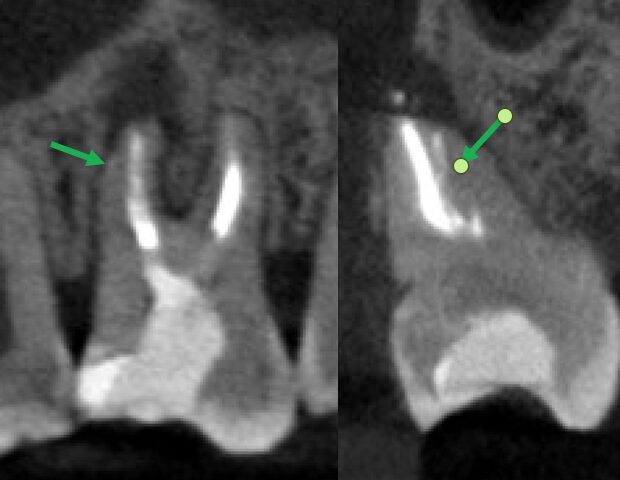

術前、右上2に大きな透過像(黄色矢印、炎症の黒い影)と左上1にも透過像(赤矢印)が見られます。腫れの原因は、歯髄壊死と根尖性歯周炎と診断し、まずは根管治療を行いました。左上1の根尖も透過像(緑矢印)がありましたが、歯髄の反応は正常でしたので歯髄壊死とは診断せず治療は行いません。

• 根管治療後4ヶ月、左上1の透過像(赤矢印、黒い影)は小さくなり治癒傾向が確認できますが、右上2(赤矢印)は以前より広がってきていて、腫脹の再発がありました。非治癒判定となり、次の治療法として歯根端切除術を行うこととなりました。歯根端切除術を行わない医院ではこの時点で抜歯が宣告されてしまうでしょう。

• 歯根端切除前と術後1年のCBCT画像、病変はなくなり骨の再生を認め治癒が確認されました。

• 別の角度のCBCT画像、骨の壁が全くない状態から1年でかなりの骨の再生が見られます。

• 別の角度のCBCT画像、骨の壁の再生がはっきりとわかります。